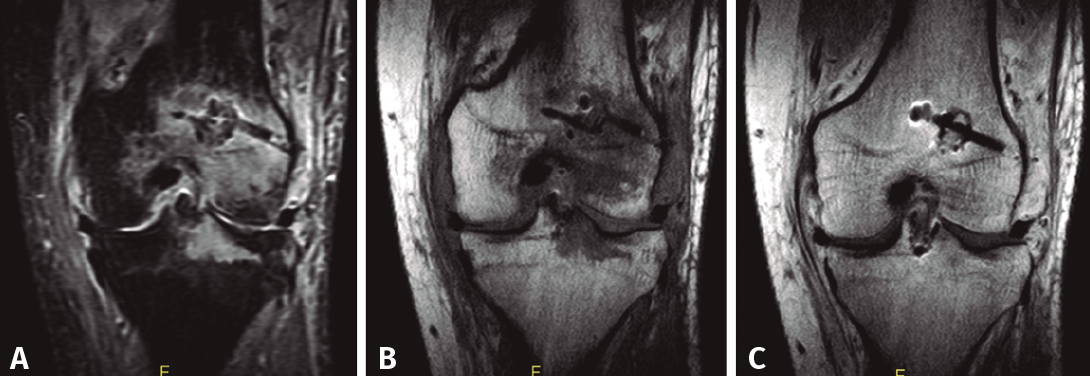

Figura 2. RM en un caso de artritis séptica tras reconstrucción de LCA. A: supresión grasa; B: sin contraste; C: con contraste.

En el diagnóstico de esta complicación es de gran utilidad la RM de rodilla, a ser posible con gadolinio (Figura 2), aunque, como toda prueba complementaria, no es imprescindible y en ningún caso debe retrasar la realización del tratamiento basado en antibioterapia y artroscopia de desbridamiento tan pronto exista una sospecha firme. La resonancia magnética es la mejor técnica de imagen para el diagnóstico de la artritis séptica. Es la más sensible de todas las pruebas radiológicas, cercana al 100%, y permite el diagnóstico precoz de la infección, siendo positiva a las 24 horas de iniciarse el cuadro. En la RM es posible ver la presencia de derrame articular, abscesos, engrosamiento de la sinovial, edema de médula ósea, miositis, celulitis, osteomielitis, etc. Es igualmente útil para valorar la posible afectación de la plastia y/o de la superficie condral y permite el seguimiento del proceso clínico. La limitación de la RM es su baja especificidad (78-82%). De manera que ninguna de las alteraciones encontradas en el estudio es lo suficientemente específica para el diagnóstico de la artritis séptica, que debe confirmarse con los estudios microbiológicos del cultivo del líquido articular y/o de las muestras de tejido obtenidas durante el desbridamiento artroscópico.